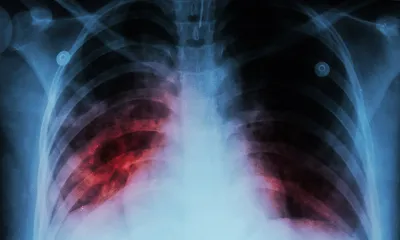

Characterising virulence and AMR in Mycobacterium tuberculosis

There are over 10 million new cases of TB per year, 600,000 of which were caused by multidrug‑resistant (MDR) strains of Mycobacterium tuberculosis that are resistant to the first‑line drugs of rifampicin and isoniazid1.

More worrying still is the increase in extensively drug‑resistant (XDR) strains that exhibit additional resistance to other classes of drugs. The mechanisms underlying the development of highly transmissible XDR strains are not fully elucidated and studies using short‑ read sequencing technology have limited capacity to resolve the structural variations, gene duplications and repetitive regions which may contribute to resistance, virulence and transmission. To combat these challenges, researchers at The University of Queensland, Australia, are utilising the long sequencing reads provided by nanopore technology to provide a more comprehensive understanding of the evolutionary mechanisms underlying the emergence of highly transmissible strains of M. tuberculosis2.